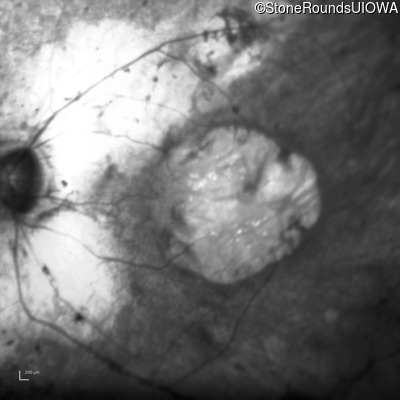

Infrared Fundus Photograph - Left - 20/100 +1

Exemplar